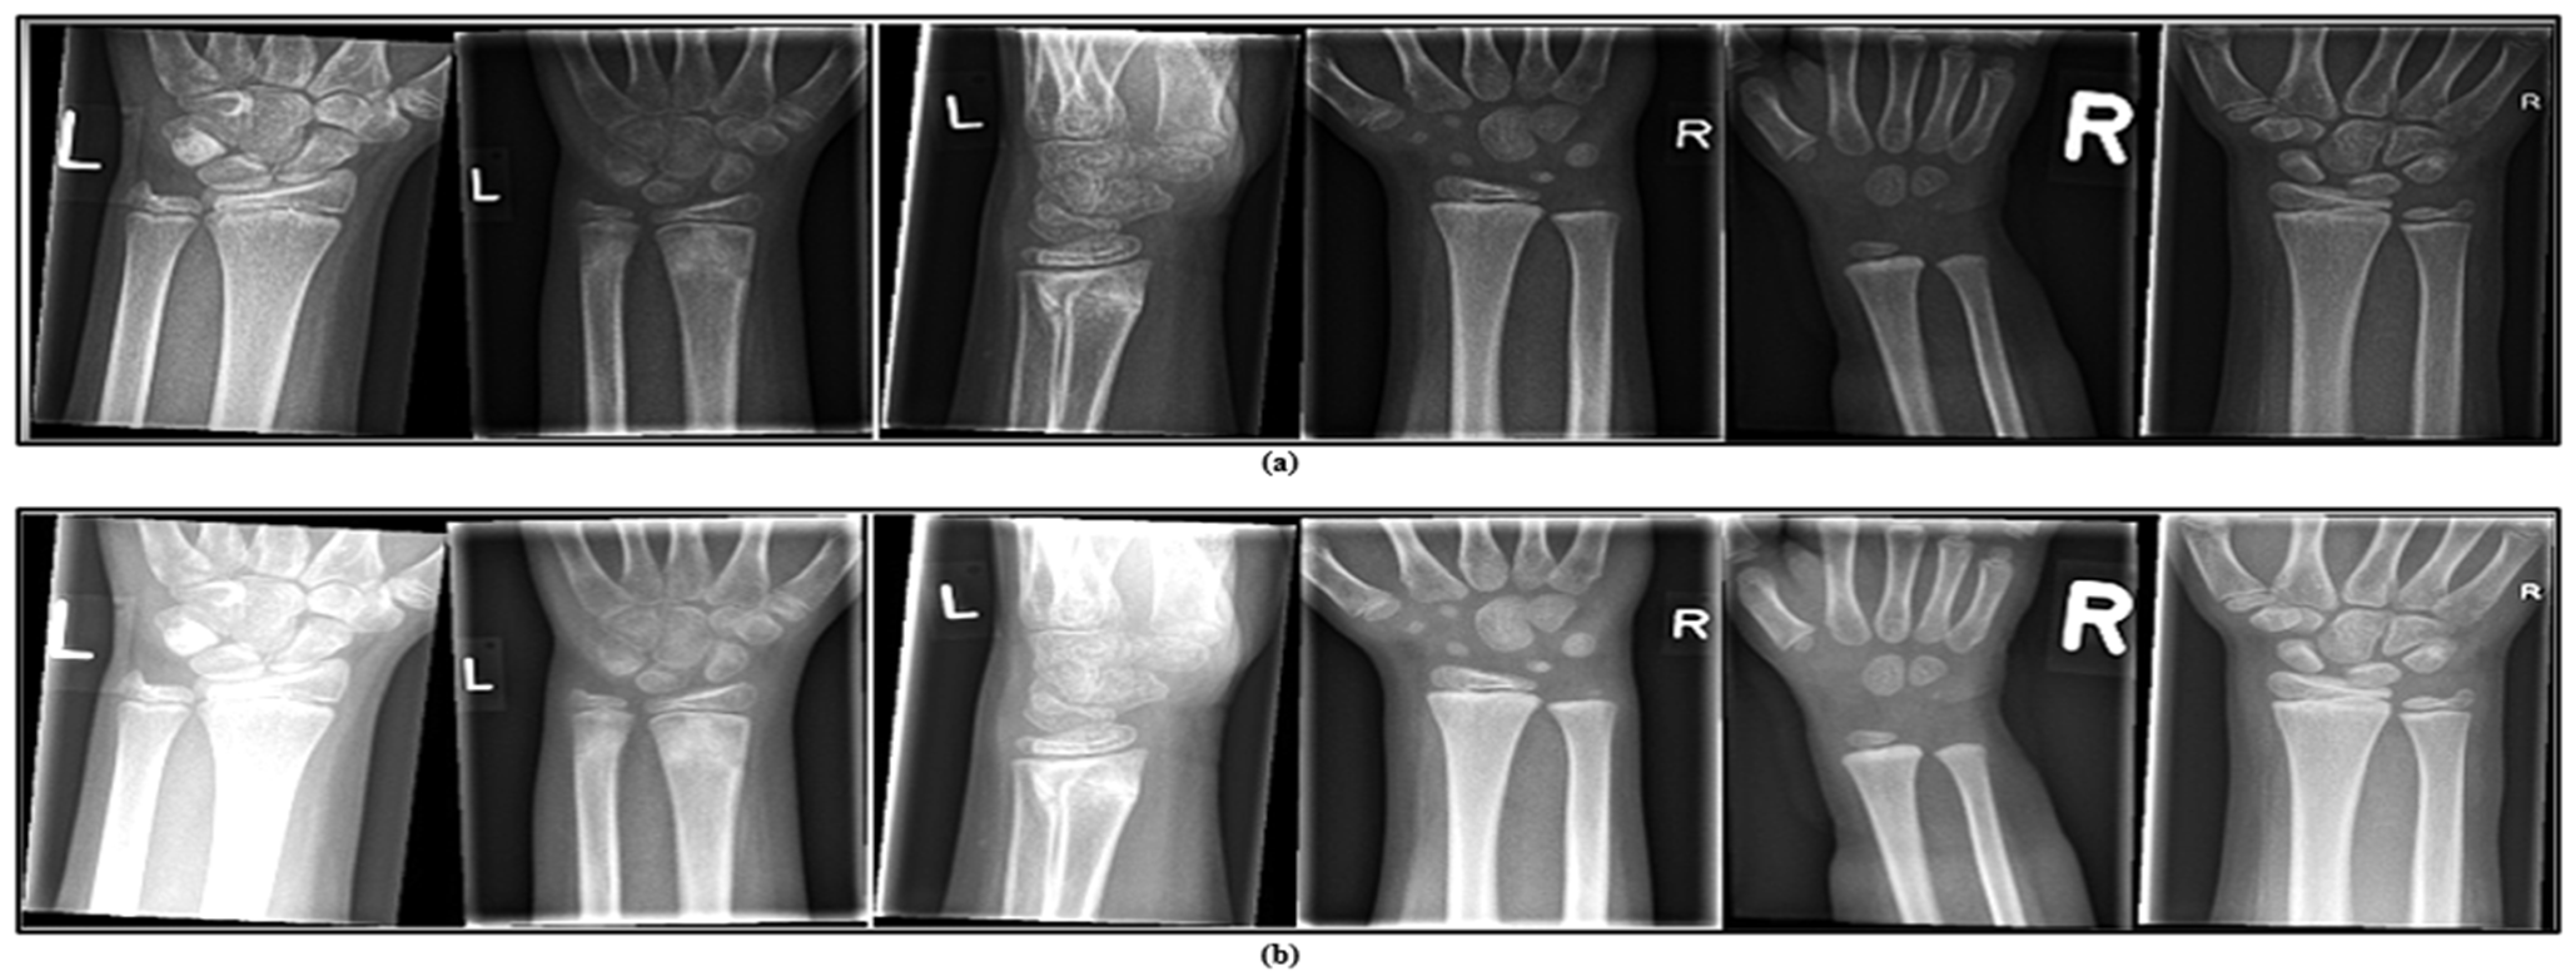

In this experimental analysis, we utilized the GRAZPEDWRI-DX dataset [44], containing 20,327 wrist X-ray images. The images, stored in PNG format, were gathered from (6091) pediatric patients between 2008 to 2018 at the Pediatric Surgery Department of University Hospital Graz in Austria. The patients in this dataset are between 2 and 19 years old, with an average age of 10.9 years. It includes 2688 female patients, 3402 male patients, and one patient whose gender is not specified. Several pediatric radiology physicians used lines, bounding boxes, and polygons to mark the diagnosed conditions, such as fractures, periosteal reaction, and other pathologies in each image. For our study, we specifically selected the subset of images annotated with bounding boxes in the YOLO format, which includes eight different fractured classes of the dataset: Text, Fracture, Metal, Bone anomaly, Bone lesion, Periosteal reaction, Pronator sign, and Soft tissue. Following the data splitting and augmentation method, the dataset publisher did not provide some of the predefined splits, so we randomly distributed the dataset into three sections: training with 70% as 14,141 images, validation with 20% as 4133 images, and testing with 10% as 2053 images, as shown below in Figure 4.

- This dataset is general, containing 20,327 labelled and categorized images, and is ideal for developing and testing computer vision models.

- The dataset includes a wide variety of images capturing early bone development in children.

- Reviewing wrist development at this stage provides important insights for identifying, managing, and preventing abnormalities that might not be noticeable in adult wrists.

4.3. Data Augmentation

Figure 5.

Representation of pediatric wrist X-rays with data augmentation presented through two sets of images: (a) shows the image after adding modifications and (b) shows the original image.

The apparent brightness difference between Figure 5a,b may be influenced by several factors, including figure layout, rendering settings during export, or display-specific contrast scaling. Although Figure 5a may visually appear brighter at first glance, we confirm that Figure 5b corresponds to the image generated using the defined augmentation parameters: X = 1.5 (contrast scaling factor) and Z = 40 (brightness offset).